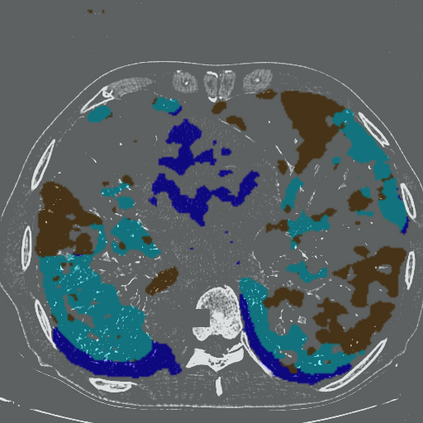

The novel coronavirus disease 2019 (COVID-19) has been spreading rapidly around the world and caused significant impact on the public health and economy. However, there is still lack of studies on effectively quantifying the lung infection caused by COVID-19. As a basic but challenging task of the diagnostic framework, segmentation plays a crucial role in accurate quantification of COVID-19 infection measured by computed tomography (CT) images. To this end, we proposed a novel deep learning algorithm for automated segmentation of multiple COVID-19 infection regions. Specifically, we use the Aggregated Residual Transformations to learn a robust and expressive feature representation and apply the soft attention mechanism to improve the capability of the model to distinguish a variety of symptoms of the COVID-19. With a public CT image dataset, we validate the efficacy of the proposed algorithm in comparison with other competing methods. Experimental results demonstrate the outstanding performance of our algorithm for automated segmentation of COVID-19 Chest CT images. Our study provides a promising deep leaning-based segmentation tool to lay a foundation to quantitative diagnosis of COVID-19 lung infection in CT images.

翻译:2019年新的冠状病毒疾病(COVID-19)在全世界迅速蔓延,对公共卫生和经济产生了重大影响;然而,对于有效量化COVID-19造成的肺感染,仍然缺乏研究;作为诊断框架的一项基本但具有挑战性的任务,分解在通过计算断层摄影(CT)图像测量的COVID-19感染的准确量化方面发挥着关键作用;为此,我们提出了对多个COVID-19感染区域进行自动分解的新型深层次学习算法。具体地说,我们利用综合残余变异学来学习一种稳健和直观的特征表征,并运用软关注机制来提高模型的能力,以区分COVID-19的症状。用公共CT图像数据集,我们验证了拟议的算法与其他相竞方法的功效。实验结果表明,我们自动分解COVID-19 Chest CT 图像的算法表现出色。我们的研究提供了一个充满希望的深度精细分解工具,为CT 图像中COVID-19肺感染的定量诊断奠定了基础。